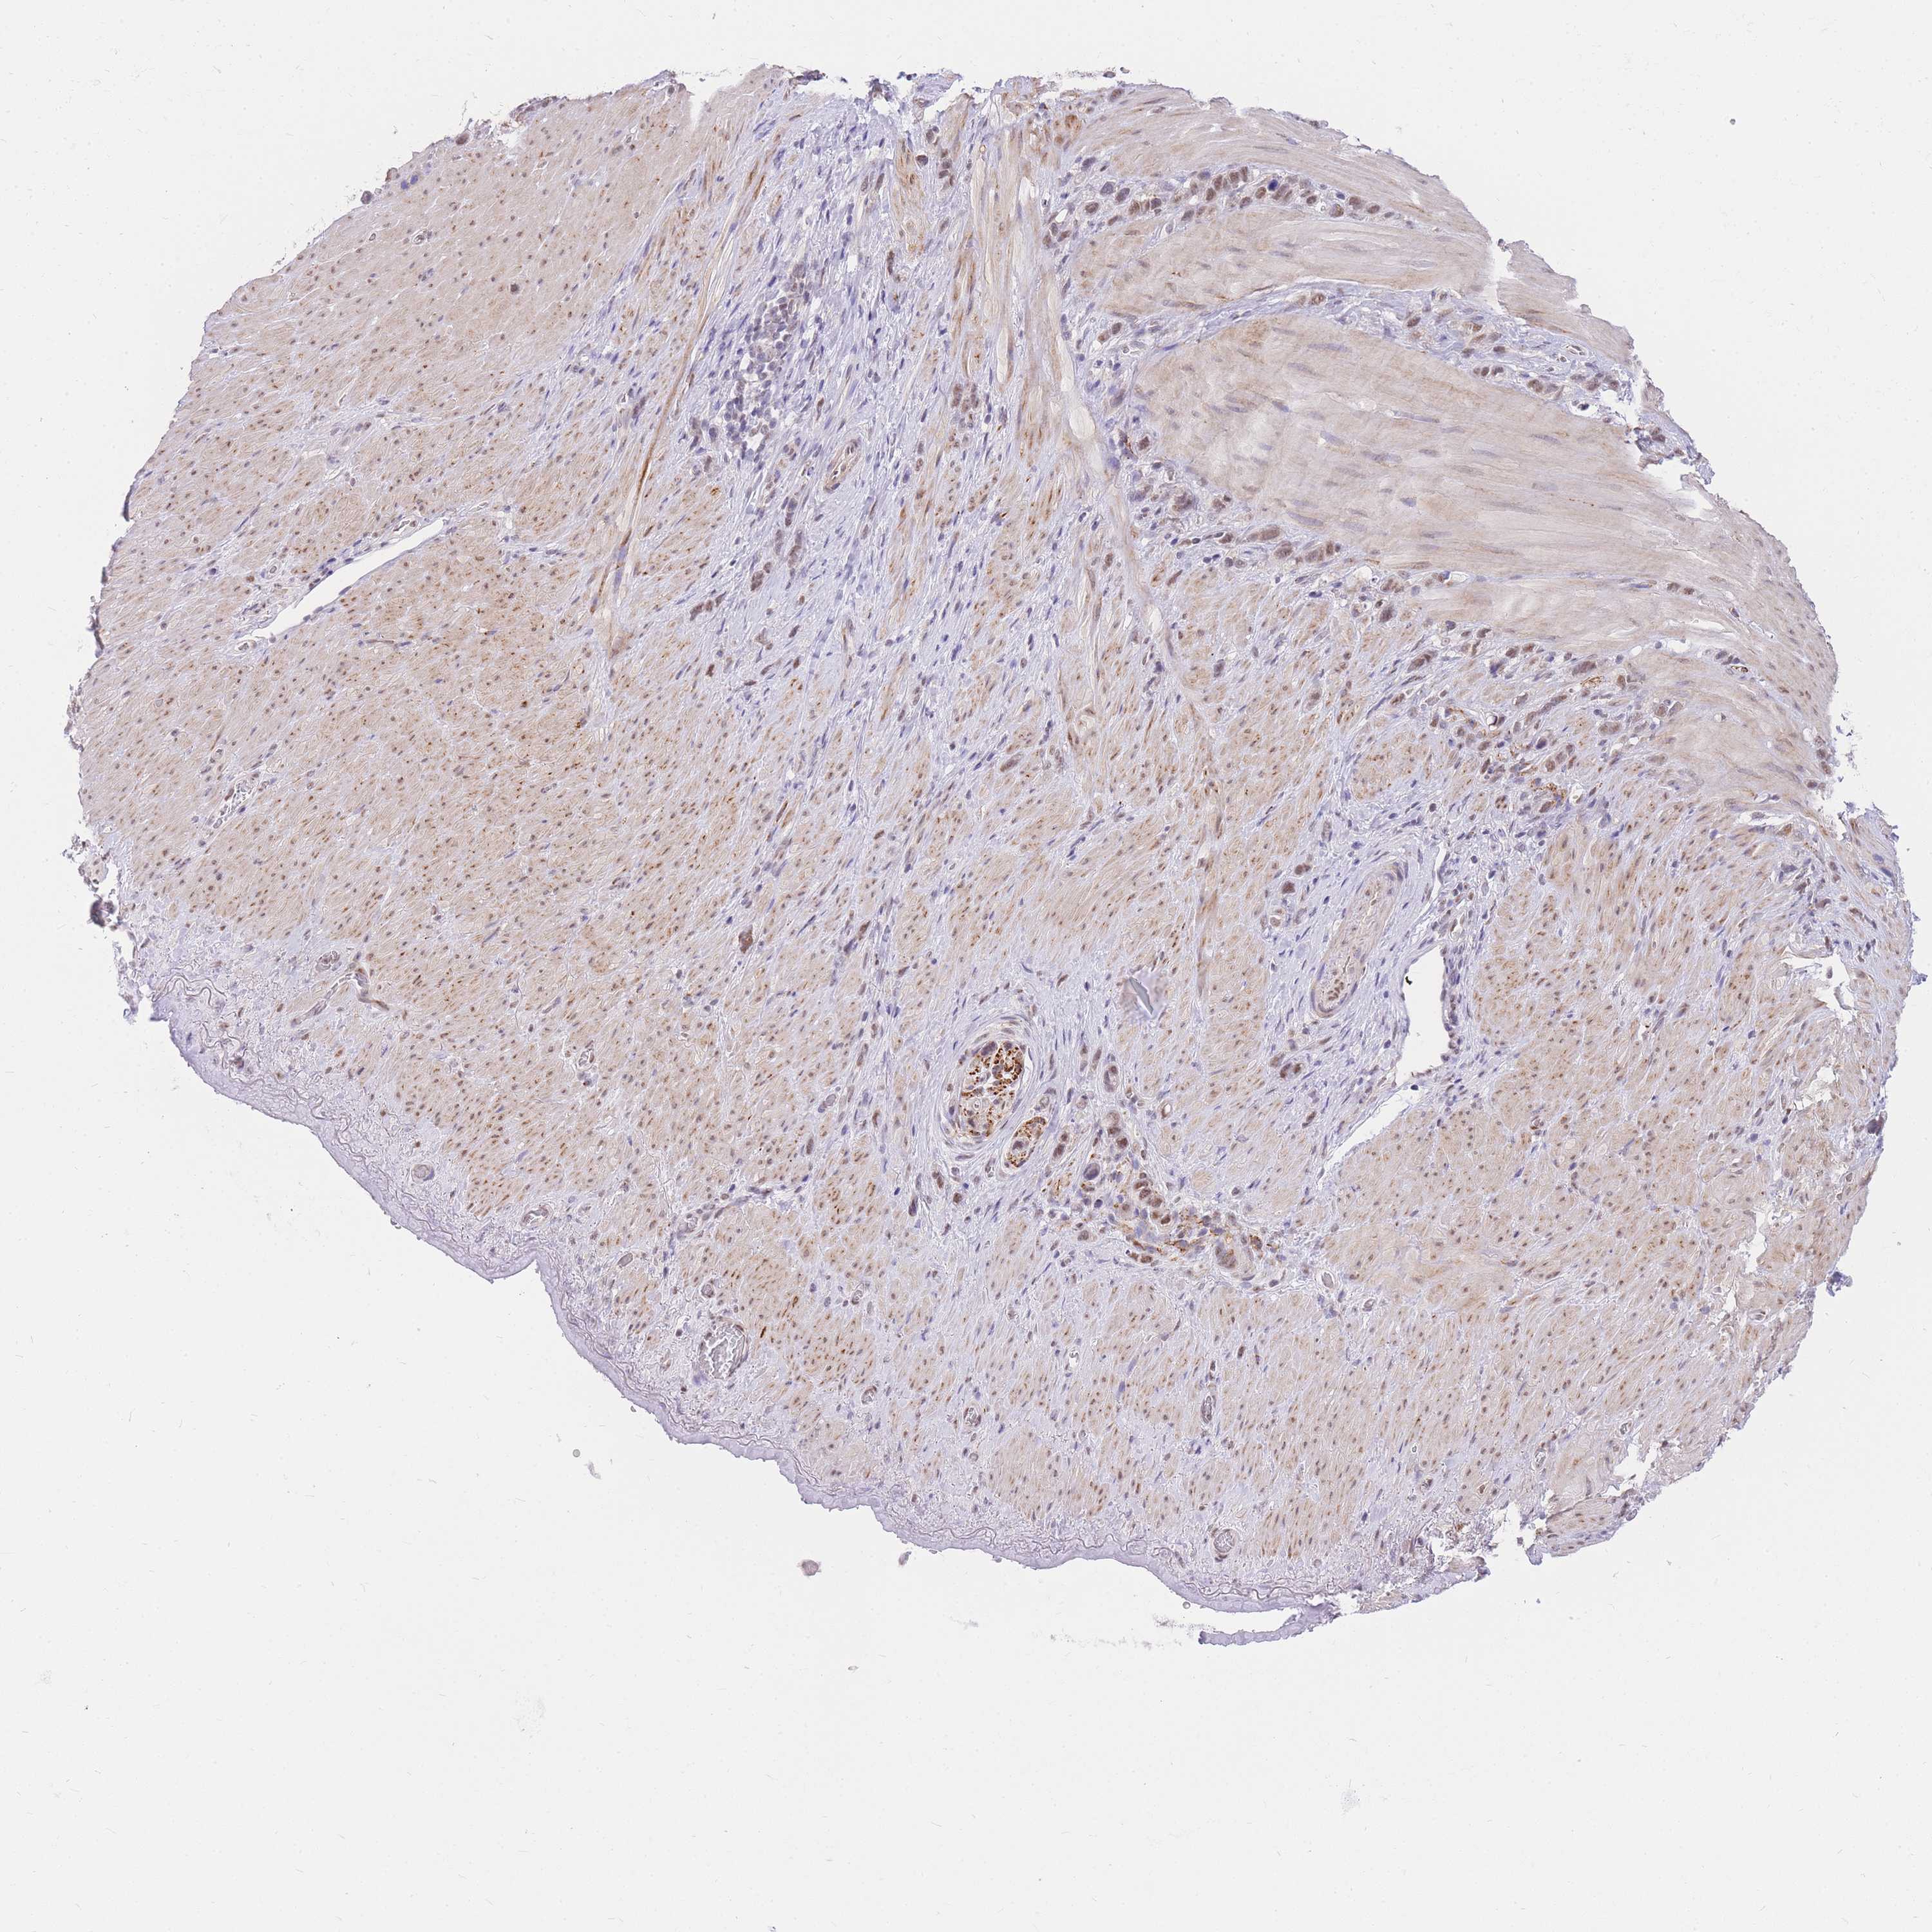

STOMACH CANCER - Protein expressioni

A mouse-over function shows sample information and annotation data. Click on an image to view it in a full screen mode. Samples can be filtered based on level of antibody staining by selecting one or several of the following categories: high, medium, low and not detected. The assay and annotation is described here.

Antibody stainingi

Antibody staining in the annotated cell types in the current human tissue is reported as not detected, low, medium, or high, based on conventional immunohistochemistry profiling in selected tissues. This score is based on the combination of the staining intensity and fraction of stained cells.

Each image is clickable and will lead to virtual microscopy that enables deeper exploration of all samples and also displays staining intensity scores, fraction scores and subcellular localization as well as patient and tissue information for each sample.

Antibody HPA027242

Antibody HPA027328

Staining

High

Medium

Low

Not detected

Intensity

Strong

Moderate

Weak

Negative

Quantity

>75%

75%-25%

<25%

None

Location

Nuclear

Cytoplasmic/membranous

Cytoplasmic/membranous,nuclear

Adenocarcinoma, NOS